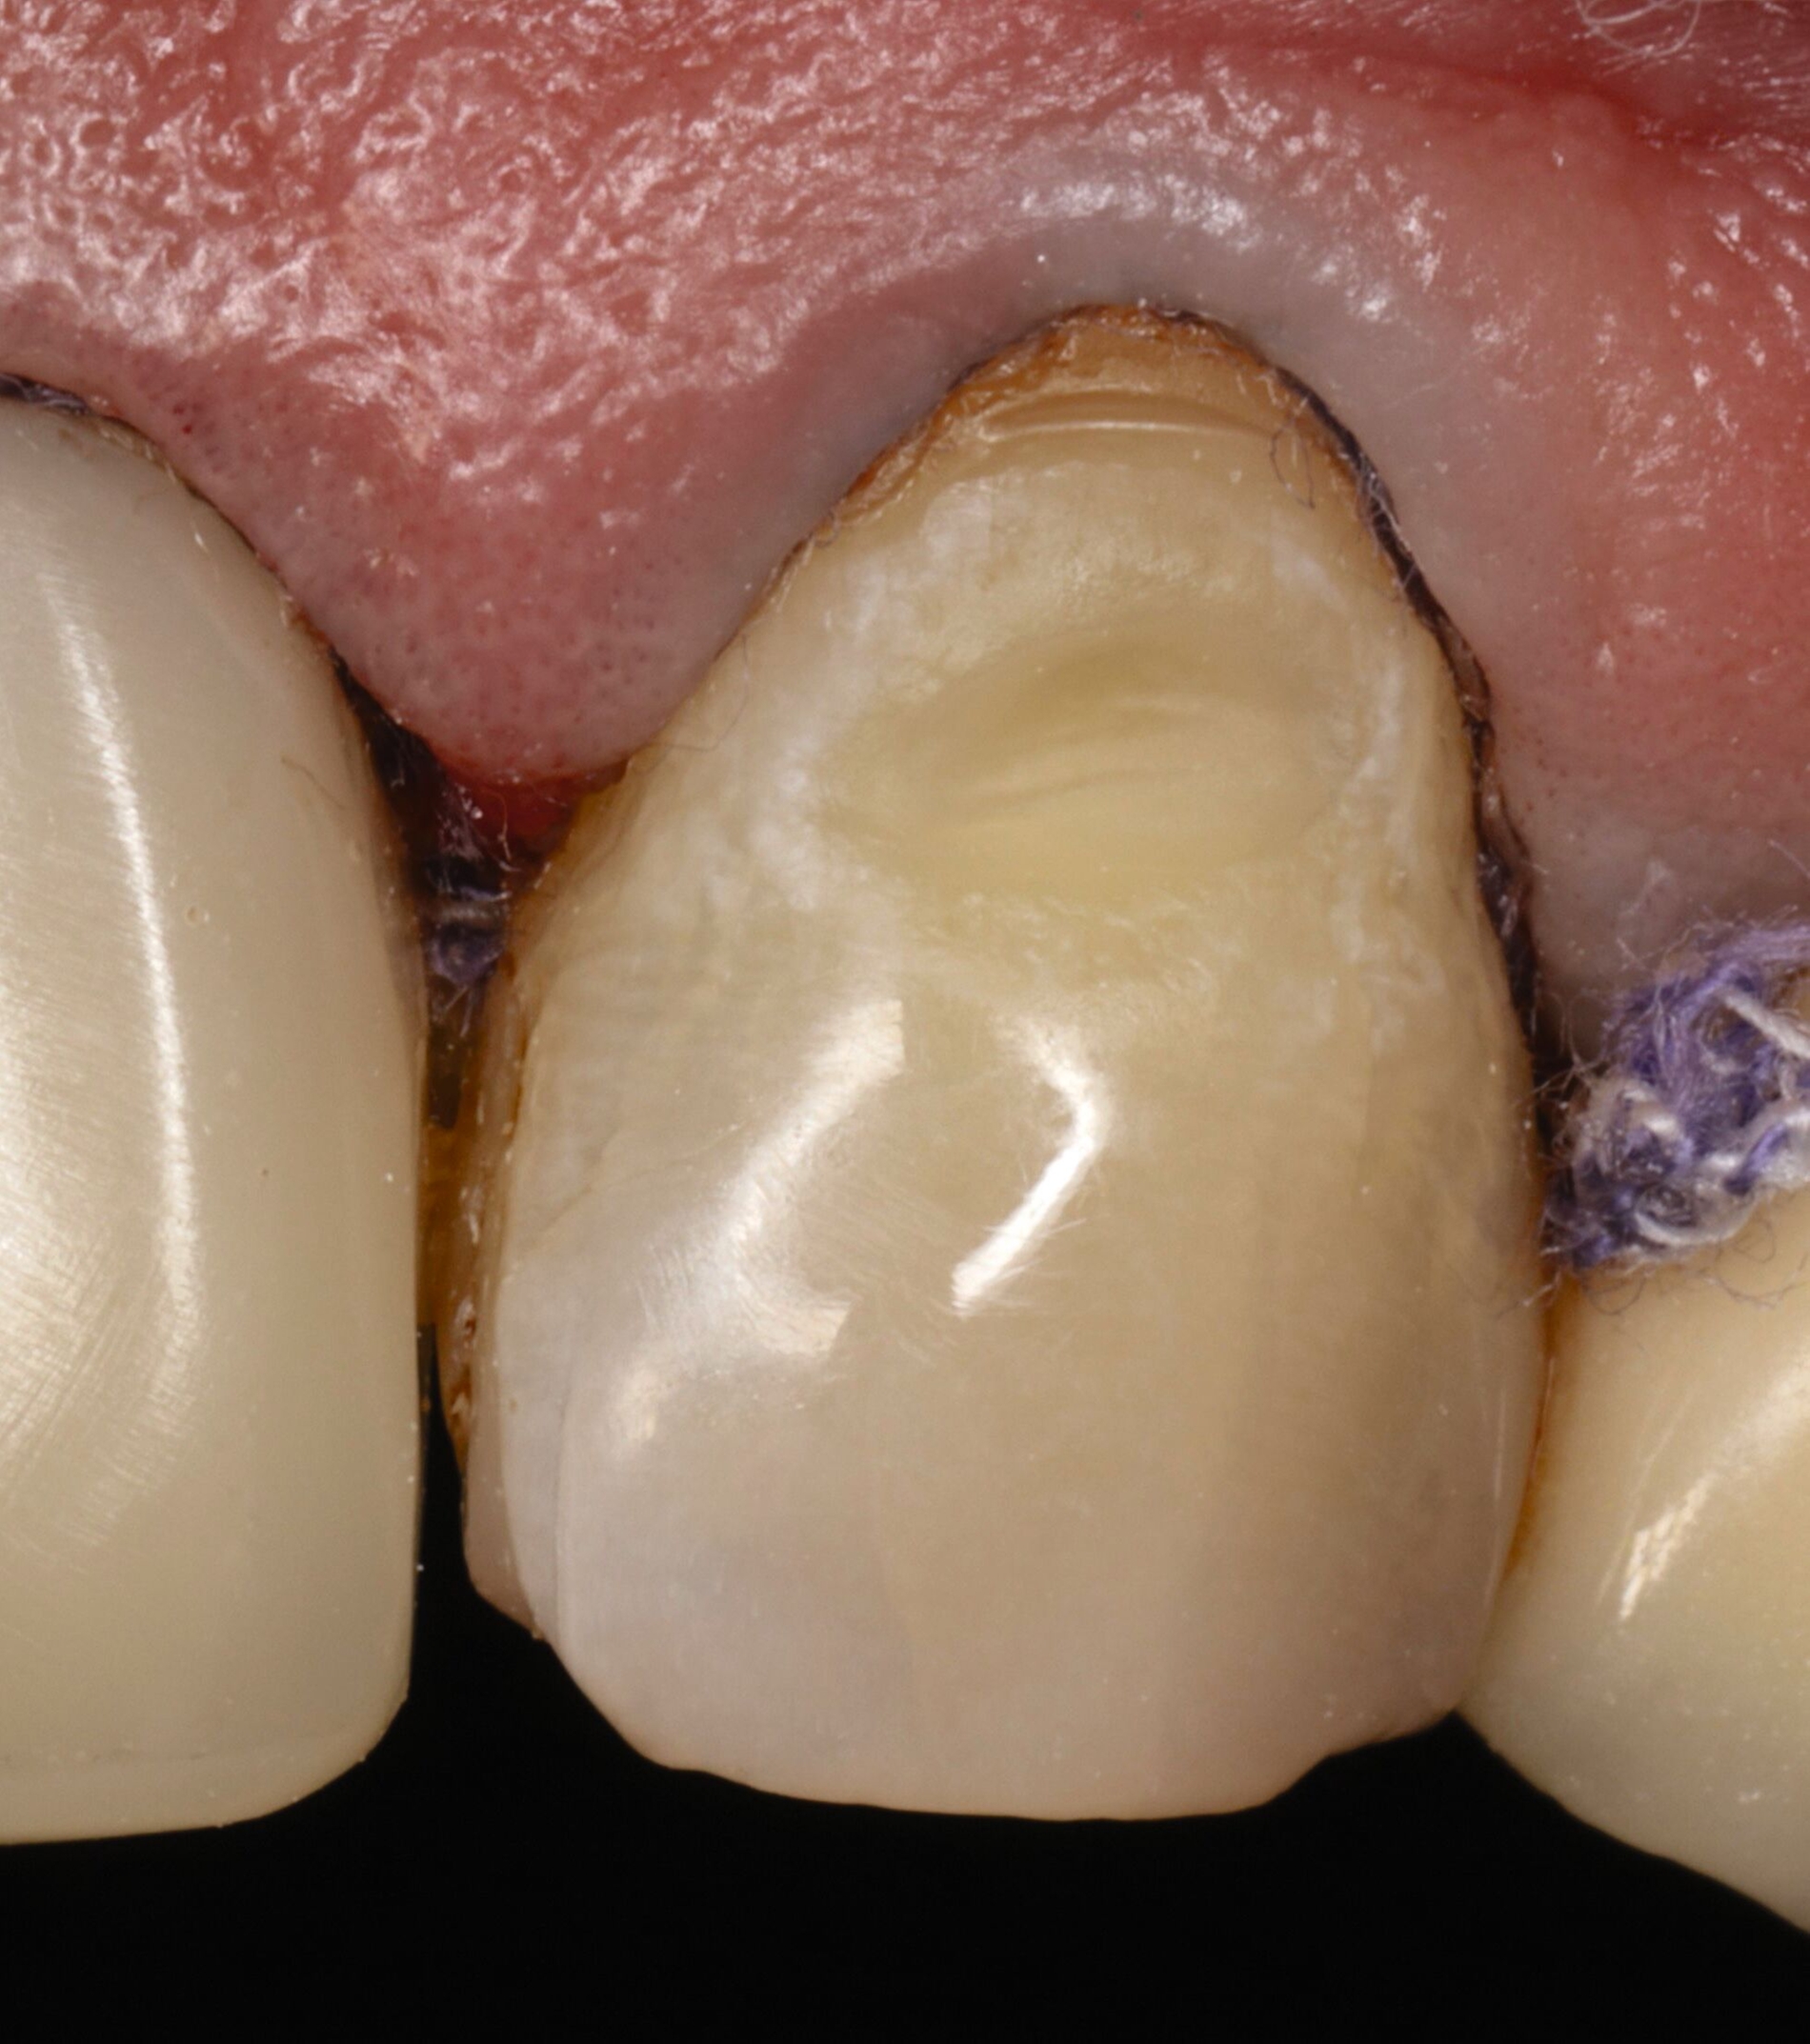

Vor 25 Jahren hatte der Patient ein Frontzahntrauma an Zahn 22 erlitten, der daraufhin mit einer Wurzelspitzenresektion und einer retrograden Amalgamfüllung versorgt worden war (Abbildung 3a). Dabei war die Zahnkrone mit einer keramisch verblendeten Stiftkrone aus Nichtedelmetall rekonstruiert worden, die nun aufgrund von Sekundärkaries insuffizient und gelockert war, jedoch keine Beschwerden verursachte. Klinisch wies der Zahn eine sehr kurze klinische Krone ohne ausreichendes Ferruledesign auf (Abbildung 5a) [Naumann et al., 2018a; Naumann et al., 2018b]. Neben dem Verdacht auf einen obliterierten mittleren Wurzelkanalabschnitt gab es röntgenologisch keinen Hinweis auf apikale Osteolysen oder parodontale Auffälligkeiten (Abbildung 3b). Der Patient entschied sich trotz des erhöhten Zahnhartsubstanzdefekts für den Zahnerhalt durch einen adhäsiv verankerten Kompositaufbau.

Für die restaurative Therapie von Zahn 22 wurde die alte Stiftkrone entfernt und die Stiftbohrung an die neue Indikation angepasst (Abbildungen 5a und 5b). Die Zahnkrone wurde dabei in drei Phasen wiederhergestellt: adhäsives Zementieren eines konfektionierten Glasfaserstifts, Stumpfaufbau und Modellation einer direkten Kompositkrone mit Silikonschlüssel, Frontzahnmatrize für komplexe Situationen und Schneepflugtechnik (Abbildungen 5c bis 5e) [Urkande et al., 2023; Amaro et al., 2021; Frese, 2020; Mannocci et al., 2002; Dimitrouli et al., 2011; Opdam et al., 2003]. Im Röntgenkontrollbild zeigt sich ein suffizienter Stiftaufbau (Abbildung 6).